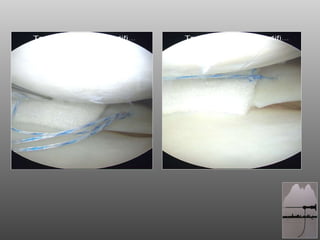

RAGAZZO DI 18aa, ATTIVO (CALCIO DILETTANTI) A 16aa SUTURA MENISCALE CORPO MENISCO ESTERNO OUT-IN  A 17 BLOCCO ARTICOLARE POST-TRAUMA: ARTROSCOPIA

RAGAZZO DI 18aa,ATTIVO (CALCIO DILETTANTI) A 16aa SUTURA MENISCALE CORPO MENISCO ESTERNO OUT-IN A 17 BLOCCO ARTICOLARE POST-TRAUMA: ARTROSCOPIA